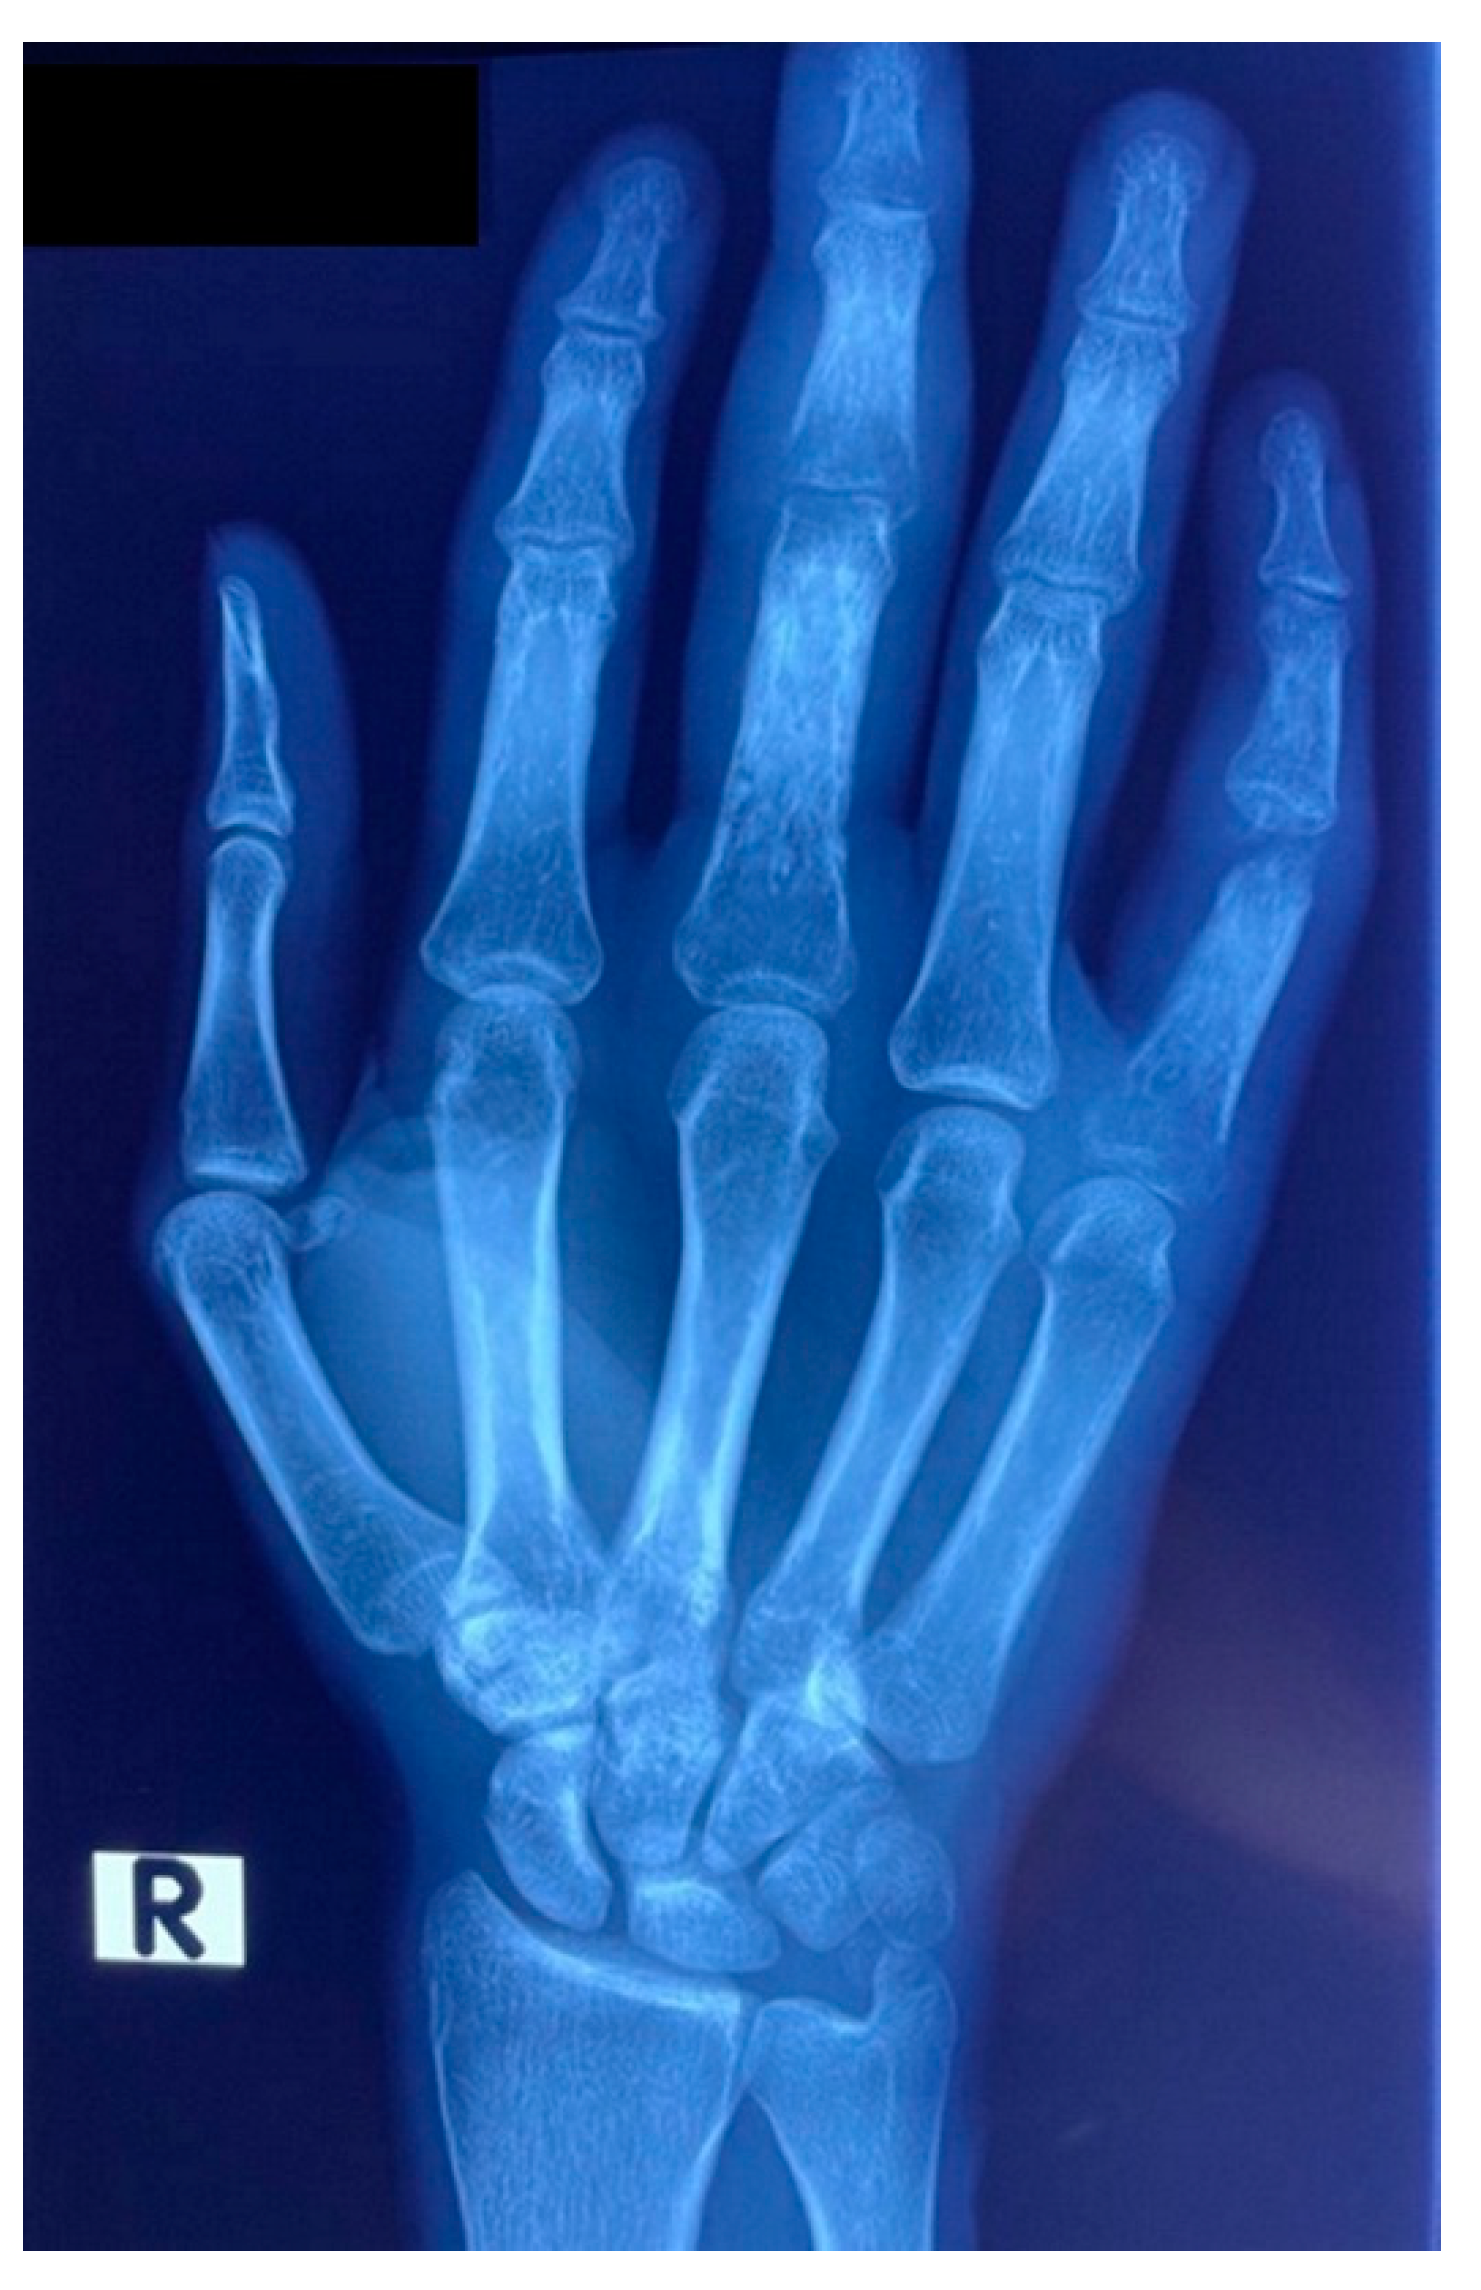

On initial clinical examination, the patient appeared wasted and chronically ill. He had generalized shotty lymphadenopathy and numerous subcutaneous nodules involving his anterior chest (Figure 1), arms (Figure 2 and Figure 3) and lower limbs. The lesions were noted to begin as papules, progress to nodules and then spontaneously ulcerate and form scabs. There was synovitis of the small joints in his right hand, as well as dactylitis (Figure 4). The cardiorespiratory, gastrointestinal and neurological examinations were all unremarkable. Of note, there was no evidence of a chronic meningitis or any focal neurological deficits. Formal ophthalmic assessment revealed an old inactive uveitic process affecting the right eye, with no evidence of keratitis in either eye. Initial dermatological clinical assessment included a differential diagnosis of lymphoma, deep fungal infection and syphilis.

Routine laboratory results on admission showed a normocytic anaemia, lymphopenia, a raised C-reactive protein of 141 mg/L and a normal procalcitonin of 0.09 μg/L. The CD4 cell count was 5 cells/μL and an HIV viral load was 110,000 copies/mL, confirming immunological and virological treatment failure, respectively. Reflex serum cryptococcal antigen screening and a Treponema pallidum antibody test were negative. Contrast-enhanced CT and MRI brain imaging, and cerebrospinal fluid examination did not reveal any abnormalities. A bone marrow aspirate and trephine biopsy excluded an infiltrate, and the anaemia was thought to be secondary to HIV infection. Of note, the admission chest X-ray revealed a nodular infiltrate in the lower lobe and lingula of the left lung (Figure 7) and the X-ray of the patient’s right hand demonstrated a periosteal reaction in the third proximal phalanx and osteolysis of the fifth proximal interphalangeal joint (Figure 8), which suggested a systemic process with multiorgan involvement.

Figure 4. Patient’s right hand on admission, showing joint and finger swelling.

Figure 8. X-ray of patient’s right hand, demonstrating a periosteal reaction in the 3rd proximal phalanx and osteolysis of the 5th proximal interphalangeal joint.